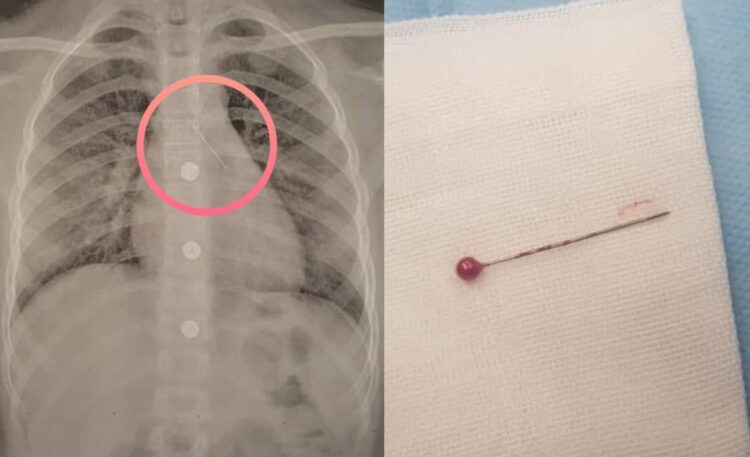

첫 번째 사례는 10세 여아가 금속 핀을 입술 사이에 물고 있다가 실수로 흡입한 사고였다. 여아 핀을 삼킨 뒤 갑작스러운 기침이 났다. 이후 가슴뼈 뒤쪽 날카로운 통증이 발생해 응급실을 찾았다. 심호흡할 때, 침을 삼킬 때 통증이 더 심하다고 했다. 엑스레이 촬영에서 가슴 부위 핀 모양 이물질이 있는 게 확인됐다. 의료진은 전신마취 하에 기관지 내시경 집게로 핀을 제거했다. 이후 24시간 후 여아는 문제없이 퇴원할 수 있었다.

두 번째 사례는 14세 남아가 병원을 찾기 2개월 전 공예활동 중 입술 사이에 뭉툭한 바늘 세 개를 물고 있다가 갑자기 숨을 들이마실 때 실수로 바늘 한 개를 흡인한 사고였다. 남아는 최근에야 기침과 간헐적으로 혈액 섞인 가래가 나오는 증상이 4일 지속돼 외래 진료실을 방문했다. 진찰 결과, 왼쪽 흉부에서 국소적인 천명음(숨을 쉴 때 좁아진 기관지를 따라 공기가 통과할 때 들리는 쌕쌕거림)이 들렸다. 엑스레이 촬영 결과 왼쪽 폐에 바늘로 추정되는 이물질이 보였다. 의료진은 기관지 내시경으로 왼쪽 기관지에 있는 바늘을 제거했다. 남아는 증상이 호전 된 후 48시간 후 퇴원했다.